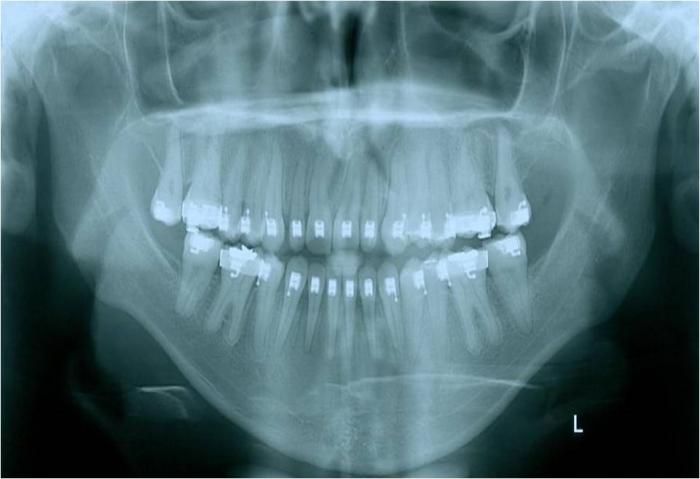

Rx após a cirurgia - Clínica Cliniface

Rx após a cirurgia